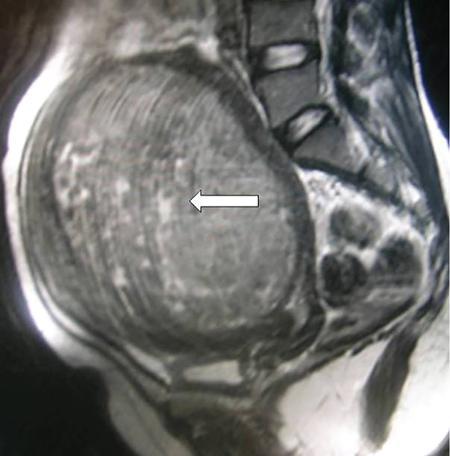

Venkatraman Indiran Bridging vessel sign Multiple vascular channels (white arrows) connecting uterus (black arrow) to an adjacent pelvic mass on imaging studies, is known as the ‘bridging vessel’ or ‘bridging vascular’ sign. Originally described on colour Doppler imaging, but also seen on computed tomography (CT) or magnetic resonance imaging (MRI). Helps in differentiating a mass of uterine origin, typically a subserosal fibroid, from other pelvic masses. Sensitivity and specificity of ‘bridging vessel sign’ in identifying subserosal fibroids range from 90% to 100%. (Best seen when subserosal fibroid is larger than 3 cm in diameter.) Ovarian masses invading the uterus may rarely produce a falsely positive bridging vessel sign. Broccoli sign Submucosal uterine leiomyoma prolapsing into the endocervical canal, along with its stalk in the uterine cavity on sagittal T2-weighted images together is called as ‘broccoli sign’ (white arrow). Submucosal uterine leiomyoma Bunch of grapes Intrauterine mass with cystic spaces without any associated foetal parts on ultrasound (white arrows) classically gives a ‘snow storm’ or ‘bunch of grapes’ appearance. Complete hydatidiform mole Hourglass sign Deep infiltrating endometriosis (DIE) affecting the posterior urinary bladder wall, usually in the midline, causes loss of its distensibility, resulting an hourglass configuration of urinary bladder. Deep infiltrating endometriosis (DIE) Hyperechoic line sign Normal endometrium surrounding the endometrial polyp on ultrasound appear as a hyperechoic rim on transvaginal ultrasound is called as ‘hyperechoic line sign’. Hyperechoic line sign represents a focal intracavitary lesion. Endometrial polyp Indian head dress sign/moose antler sign In deep infiltrating endometriosis (DIE), adhesions between the anterior wall of rectosigmoid and posterior wall of uterus, stretches the muscular layer of the bowel and creates an infiltrative nodule with parallel lines that extend from the adhesion to the rectosigmoid. This is called as ‘Indian head dress sign/moose antler sign’ (white arrow). This is seen on sagittal T2-weighted images as well as transvaginal ultrasound. Deep infiltrating endometriosis (DIE) Interstitial line sign An echogenic line that extends into the upper regions of the uterine horn and borders the margin of the intramural gestational sac is called as the ‘interstitial line sign’ (white arrow). Seen best on transabdominal/transvaginal ultrasound. Specific finding of interstitial pregnancy Mushroom cap sign Mushroom-shaped lesion which is seen displaced into the bowel lumen in patients with solid invasive endometriosis of the rectosigmoid colon on axial or sagittal T2-weighted MRI is called as ‘mushroom cap sign’ (red box and white arrow). Low signal intensity base of the mushroom corresponds to hypertrophy and fibrosis of the muscularis propria, whereas the high intensity cap represents oedematous mucosa and submucosa. Deep infiltrating endometriosis (DIE) Pedicle artery sign Feeding vessel sign Central vessel entering the endometrium from the surrounding myometrium colour Doppler imaging of the endometrium in endometrial polyps is called as pedicle artery sign (white arrow). Endometrial polyps in women with postmenopausal bleeding. (Sensitivity of 76.5%; specificity of 95.3%.) Popcorn ball calcification Dense, amorphous calcifications of uterine fibroids seen on the plain radiographs is called as ‘popcorn calcification’ (white arrow). Confluent, coarse calcification constitutes the most specific radiographic sign of a benign uterine fibroid; but only 10% or fewer of fibroids show calcification. Question mark sign of uterus The uterine corpus that is flexed backward with the fundus of the uterus facing the posterior pelvic compartment and the cervix directed anteriorly toward the urinary bladder, is called as question mark sign of uterus (white arrow). Also called as comma-shaped uterus. 93% specificity and 75% sensitivity in diagnosing adenomyosis uterus. Sliding organs’ sign When the uterus and ovaries glide freely over the posterior and anterior organs (such as rectum and urinary bladder, respectively) during real-time dynamic transvaginal sonography, it is called as ‘positive sliding organs’ sign’. In case of adhesions due to endometriosis, free gliding of organs is absent and is called as negative sliding sign. Snowstorm sign Grainy appearance with low-level homogeneous internal echoes which move slowly downward due to their viscosity seen in endometrioma on transvaginal ultrasound is called as snowstorm sign. Endometriomas Split fibre sign Presence of curvilinear T2 hypointense strands within the degenerated leiomyoma separated by the fluid accumulation and oedema is called as the ‘split fibre’ sign. Split fibre sign on T2-weighted MRI can be used to differentiate hydropic degeneration from other conditions like malignant change. Three-line sign or triple line sign or trilaminar appearance Shortly before ovulation, two additional bright linear echoes outline two hypoechoic layers of endometrium with a central hyperechoic line in the endometrium (white arrow). It is called as the ‘three-line sign’ or ‘triple line sign’ or trilaminar appearance. A triple-line pattern with a moderate endometrial thickness is associated with a good clinical outcome on in-vitro fertilization. Venetian blind shadowing Also known as ‘rain shower’ appearance Heterogeneous myometrial appearance due to hyperechoic heterotopic endometrial tissue and hypoechoic hyperplastic smooth muscle appearing as vertical linear bands of shadows on ultrasound is called as ‘Venetian blind shadowing’. Classically described in uterine adenomyosis; sometimes in uterine fibroids also. Bead on strings sign Thickened endosalpingeal longitudinal folds within a dilated fallopian tube without wall thickening appears as small mural nodules on cross-sectional images on ultrasound is called as ‘bead on strings’ appearance. Seen in chronic salpingitis Beaded tube Multiple constrictions along the course of fallopian tube may form due to scarring is seen in genitourinary tuberculosis and shows a ‘beaded’ appearance. Female genital tuberculosis Cogwheel sign Thickened endosalpingeal longitudinal folds within a dilated fallopian tube with thickened wall appears as small mural nodules on cross-sectional images across the long axis of the fallopian tube on ultrasound (white arrows) produce a characteristic ‘cogwheel’ appearance. Seen in acute salpingitis. The presence of thickened longitudinal folds is pathognomonic for hydrosalpinx. Cobblestone tube Rounded filling defects in cases of fallopian tube tuberculosis are called as the cobblestone pattern. Is an effective radiographic sign of intraluminal scarring and adhesions. Female genital tuberculosis Golf club tube Occlusion of the isthmus or fimbrial end of the fallopian tube and filling up of the tube with serous or clear fluid produces a moderate dilatation at the fimbrial end, produces a ‘golf club–like appearance’. Female genital tuberculosis Halo sign Thin radiolucency seen separating the loculated peritubal collection from the dilated tube, is known as the ‘halo sign’. This radiolucent halo represents the thickened wall of the tube. Female genital tuberculosis Incomplete septation sign Thin linear structures appearing to protrude into the tubular cystic adnexal structures, but not touching the opposite walls is called ‘incomplete septation sign’ of hydrosalpinx. Apparent septae are due to apposition of the inner walls of the dilated and folded fallopian tube. Hydrosalpinx Pipe stem tube Rigid contour of the fallopian tube seen in cases of fallopian tube tuberculosis is called as ‘pipe stem appearance’. Female genital tuberculosis Leash sign Typical eccentric leash of vessels on colour Doppler (white arrow) showing a low resistance placental type of flow on spectral Doppler in fallopian tube ectopic pregnancies is called as leash sign.